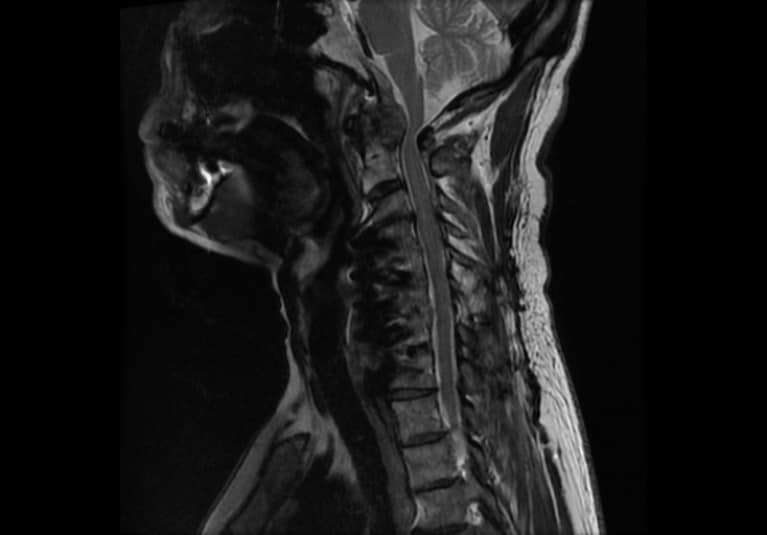

Spinal cord compression

Sagittal MRI shows kinking and compression of the spinal cord at the occipitocervical junction, with the associated cord signal change representing ongoing damage to the spinal cord.